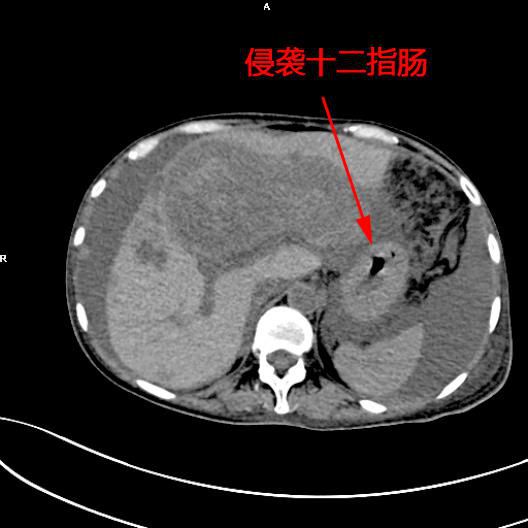

患者陳女士,57歲,汕頭潮南人,2個月前出現右上腹痛,在汕頭大型三甲醫院确診爲膽囊癌,因腫瘤爲晚期,已擴散至肝髒、十二指腸,患者放棄在汕頭治療,回家後自行采用中藥治療。近期右上腹痛加重,反複排黑便,遂來我院住院,診斷爲膽囊癌伴活動性出血。

5月11日下午,内三科主任李旭丹、影像科副主任胡志華上台施術。通過粵東領先的飛利浦DSA造影顯示,患者腫瘤供血血管豐富,膽囊動脈造影可見腫瘤染色明顯,有造影劑外溢,提示部分血管末梢有破裂出血現象,探查胃十二指腸動脈及腸系膜上動脈未見出血征像,豐富的血供使腫瘤能獲取大量的營養快速生長,血管末梢的破裂出血導緻患者反複黑便。

李旭丹主任在DSA引導下找到腫瘤的供血動脈——膽囊動脈,通過股動脈穿刺置入微導管将栓塞材料送達并釋放于腫瘤供血動脈,成功将動脈堵住,掐斷了腫瘤的供血。手術達到了預期目的,不但膽囊出血得到根除,也阻斷了腫瘤的營養供應,達到“餓”死腫瘤的目的,同時在腹腔幹灌注化療藥治療轉移病竈。